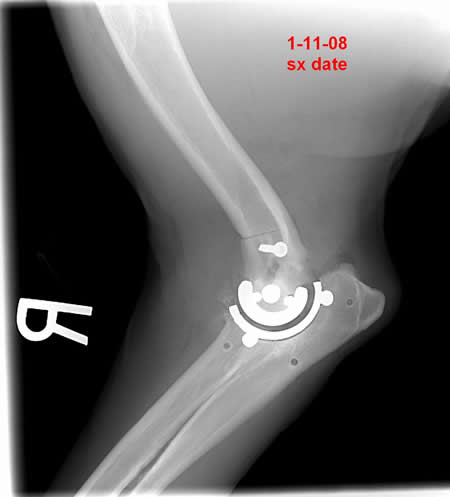

When was the first clinical case?

In July of 2007 we implanted “Otis” who was an older Labrador with many orthopedic problems. I was apprehensive, with a client owned patient, but the owner was aware of the experimental nature of the case and was frustrated with his dog’s inability to move. With two engineers in the room and a three hour surgery, I was relieved to get the implant in. I was more relieved when he walked out of the clinic three days later bearing weight well. I had researched other systems that had been discontinued after only a few cases. I was recently contacted by the owner requesting the other elbow be replaced.